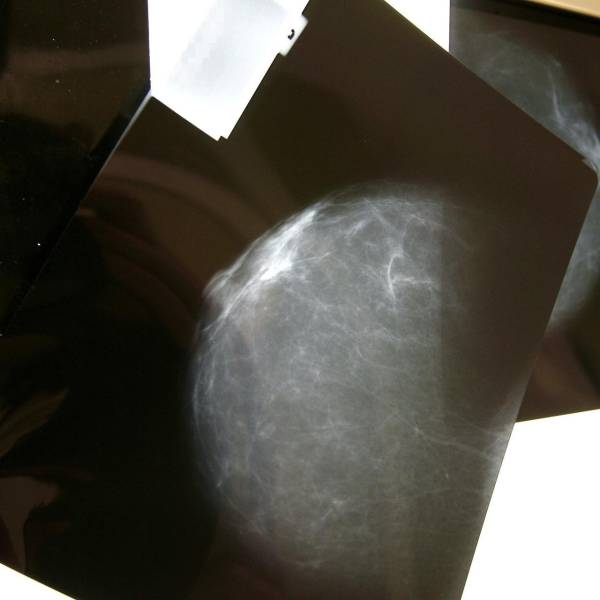

El cáncer de mama causará más de un millón de muertes en el 2050

El cáncer de mama se ha convertido en una de las principales causas de muerte entre mujeres en todo el mundo. Según la Agencia Internacional de Investigación sobre el Cáncer (IARC), una de cada 20 mujeres padecerá esta enfermedad a lo largo de su vida y una de cada 70 morirá por su causa.

En 2022 se registraron 2,3 millones de nuevos diagnósticos y 670 000 fallecimientos, pero las proyecciones indican que, para 2050, los casos aumentarán un 38 %, superando los 3,2 millones anuales, y las muertes podrían superar el millón, un incremento del 68 %.